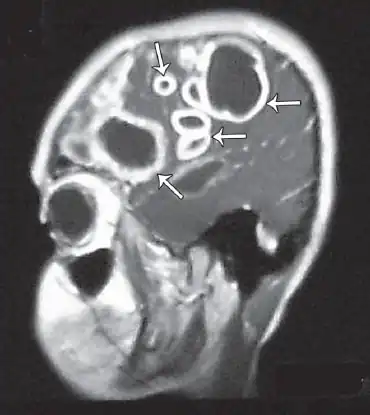

Cranial MRI revealed multiple, contrast-dense masses -abscesses -

The diagnosis of Entamoeba histolytica in the brain abscesses is difficult for several reasons. Firstly, the aerobic and anaerobic cultures generally provide negative results.[9][10] In addition, the CT results are often inconclusive and even the parasitologic stool examinations and abdominal ultrasonography often yield normal results. However, direct examination of the abscess capsule may exhibit necrotic material, foamy histiocytes, rare eosinophills and ingested erythrocytes.[11] Spheric structures may insinuate the presence of Entamoeba histolytica trophozoites with Masson's trichrome stain. Additionally, PCR based analysis of the CSF can be used to positively identify the parasite in the system .[12] Combination of CT scans and PCR based identification along with the serological methods are the current diagnostic measures for detecting Entamoeba histolytica.